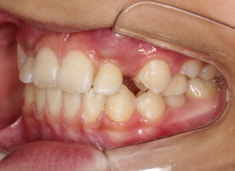

治療前

治療開始時